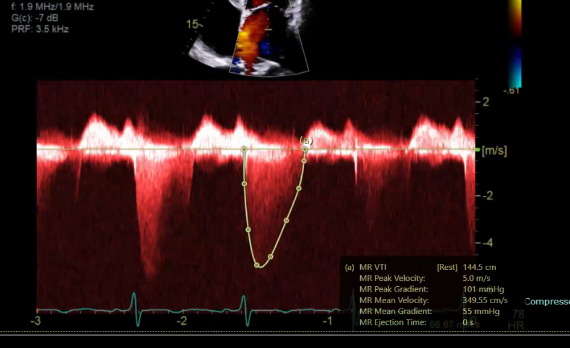

what measurement would this be

trace this measure when you get a really nice envelope, this is she MVR PISA method and measure MVR VTI (the jet is u-shaped)